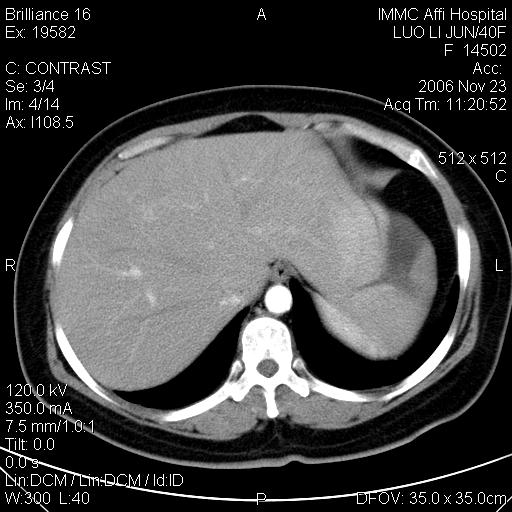

标题: CT5664:我也发一个肝脏的片子大家看看

很典型的肝癌。

典型肝癌

肝癌

速升速降,典型肝癌.

支持-----考虑肝癌----[-从片上看增强早期应该是动脉晚期即门脉早期]

是啊,典型的早出早归!

快进快出典型肝癌.

病灶好圆!可能恶性度不高。

不能除外肝细胞腺瘤吧,还是得结合病史。

很好的片子,可惜增强做的比较失败,a期时间没有把我好,实际到了静脉早期了,否则会更典型。

最终考虑是肝腺瘤